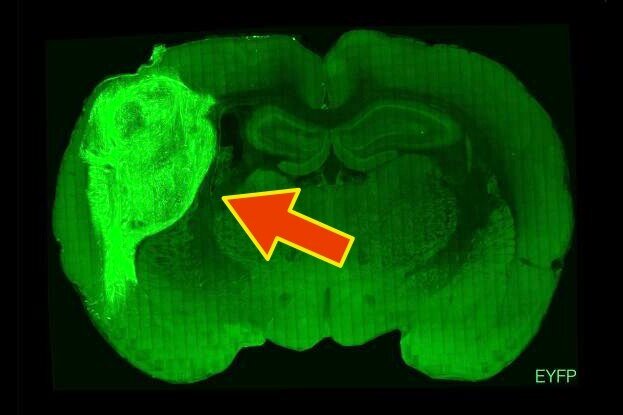

Мозговые клетки человека, растущие внутри эмбрионаStanford University

После поведенческих тестов крыс усыпили, извлекли и препарировали их мозг, что позволило исследователям наблюдать за интеграцией органоидов на клеточном уровне. Они обнаружили, что органоидные нейроны выросли намного больше, чем любые нейроны, выращенные in vitro, проникая в мозг крыс и образуя сети с нативными крысиными нейронами.